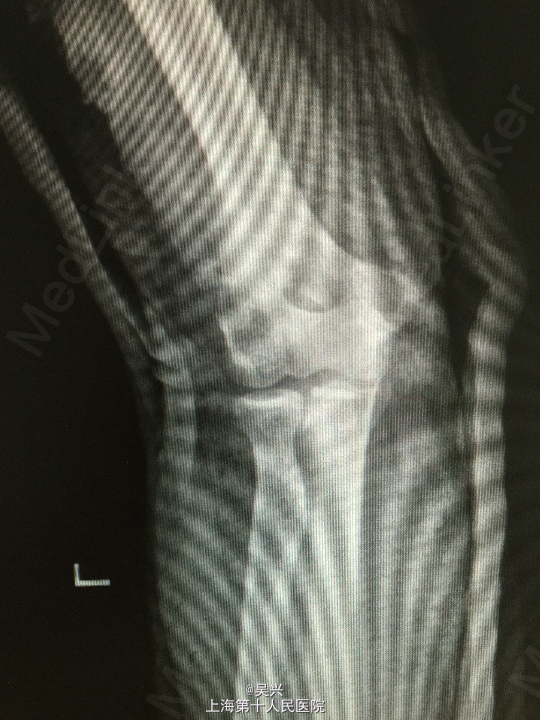

诊断:左肘恐怖三联症。 处理:术前准备,抗炎消肿治疗,术后三天行左肘正中切口显露尺骨冠状突,术中见尺骨冠状突粉碎性骨折,用两枚微型空心螺钉固定,发现屈肘位置仍有肘关节半脱位趋向。予伸肘位石膏固定,术后2周改屈肘45度位石膏固定,术后4周拆石膏,能逐渐屈肘至90度。

随访:术后1月患者肘关节稳定性良好,伸肘0度,屈肘90度,理疗辅助功能锻炼中。 讨论:肘关节脱位(半脱位)伴尺骨冠状突骨折、桡骨小头骨折称为肘关节恐怖三联症。该症存在极度肘关节不稳定,容易发生向后方、侧方脱位。一般单纯尺骨冠状突骨折极少,多伴有桡侧结构损伤和关节不稳定。肘关节恐怖三联症治疗原则一般是复位固定尺骨冠状突和桡骨小头,修复桡侧副韧带。我们术中发现固定尺骨冠状突后关节仍然不稳定,但桡骨小头因不全骨折需要石膏固定,因此不采取手术修复外侧副韧带,而是石膏固定,术后也取得较好的效果。